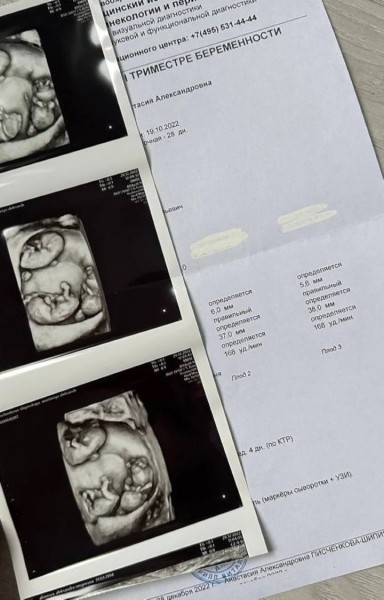

— Первое УЗИ мы делали в Гомеле. Его делала известная в области гинеколог Светлана Матвеевна Чучваго. Она сказала: «Ну-с, будем считать…» Я посмеялась, но только со временем поняла всю серьезность положения, — вспоминает Настя.

В заключениях было написано: монохориальная триамниотическая тройня. Если говорить простым языком, то это однояйцевые близнецы. Даже двое однояйцевых близнецов в природе получаются крайне редко. А трое — совсем уж редкое явление. Считается, что такое бывает один раз на 200 миллионов беременностей.